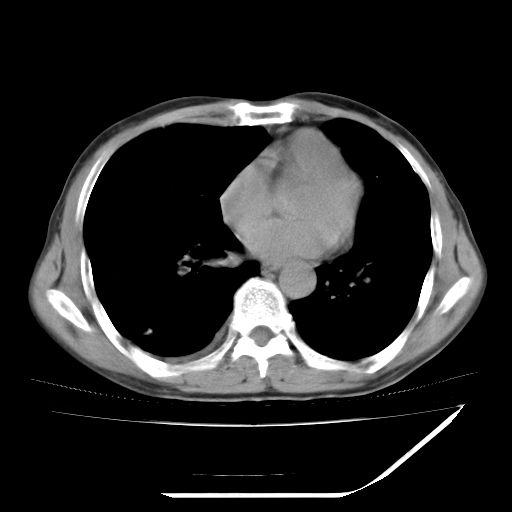

男,59岁,“结核性胸膜炎”30余年,胸部经常疼痛,多次x检查提示“肺部”炎症。腹部疼痛5日,b超提示:“肝内短管结石,余显示不清,建议进一步检查。”

两肺结核并右侧胸腔积液;脾脏、腹腔及腹膜后淋巴结结核[陈旧性];肝内胆管结石

胸部腹部都是结核(双肺。纵隔淋巴结,肝脏,脾脏,肠系膜)

两肺结核并右侧胸腔积液;脾脏、腹腔及腹膜后淋巴结结核[陈旧性];肝内胆管结石。直肠息肉?